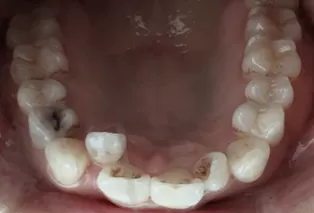

Intraoral photos